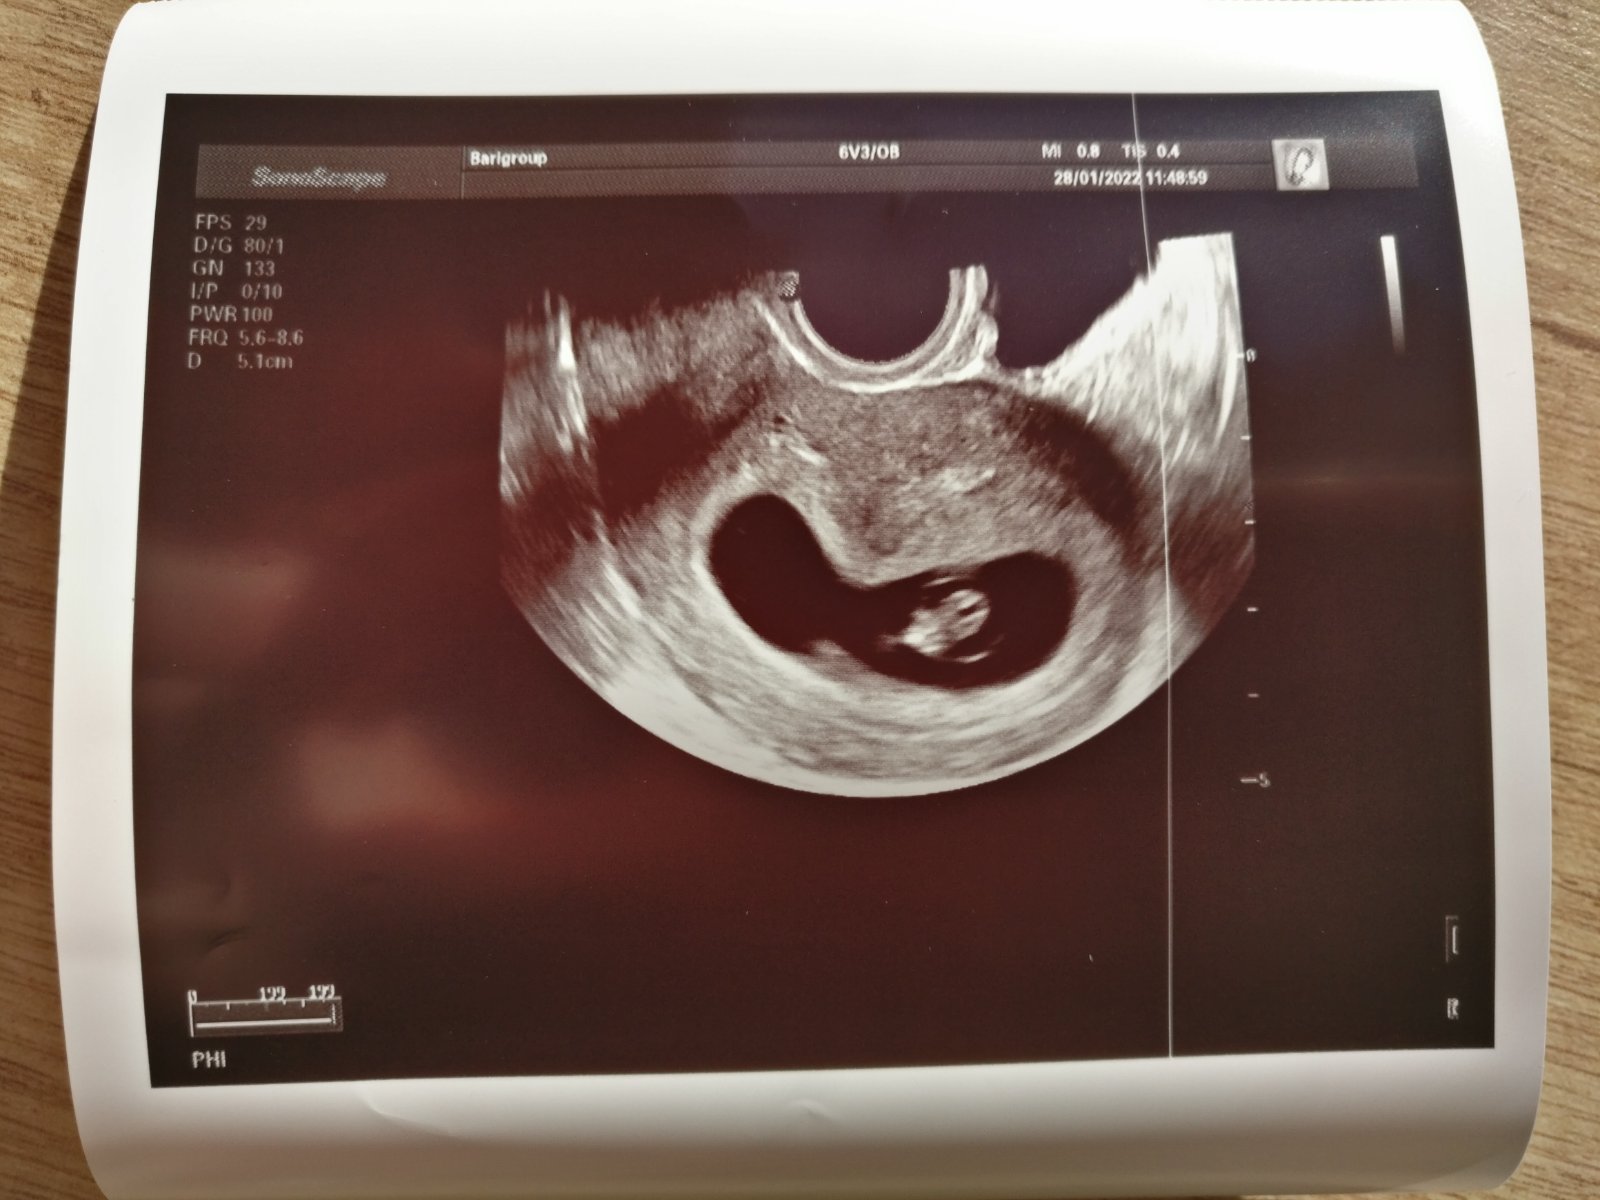

A my sa mame dobre, dakujem za opytanie 🤗...akurat nevolnosti ma trapia uz asi dva tyzdne. A celodenne..takze je pre mna teraz narocne normalne fungovat, ale pre nase fazulatko vsetko vydrzim. 🙏 V piatok som bola na kontrole a mam uz aj prvu fotecku a potvrdenu akciu srdiecka 😍🤗 malinke vyzera zatial ako mala želvička a bola to laska na prvy pohlad. Podla sona sme v osmom tyzdni 😊 tak sa len modlim aby bolo vsetko aj nadalej v poriadku.